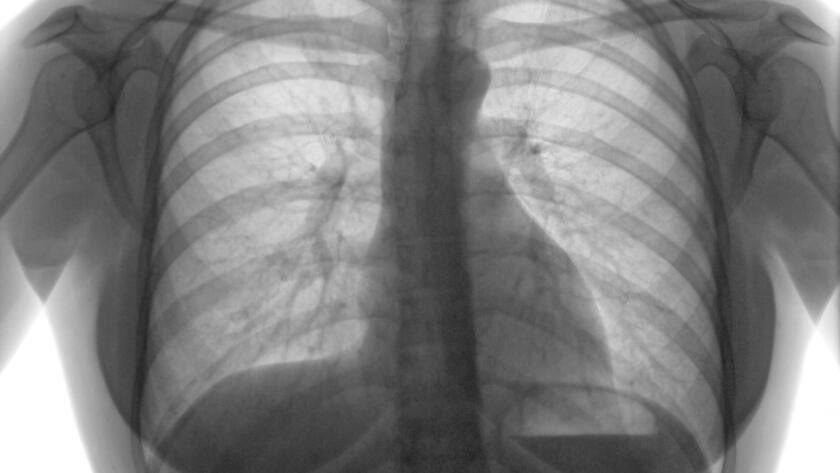

Günümüzde check-up (tarama) programlarının ve bilgisayarlı tomografinin (BT) yaygınlaşmasıyla birlikte, “akciğerde nodül” (halk arasındaki tabiriyle akciğerde leke) saptanma oranı oldukça artmıştır. Polikliniklere başvuran hastaların en büyük endişesi, raporda gördükleri bu…